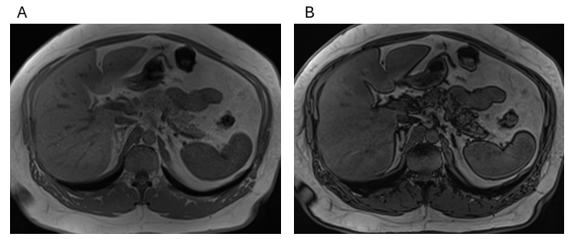

Figure 1 Moderate fat infiltration. Axial T1 Dixon GRE: In-Phase (A), Out-of-Phase (B) images. Fat interdigitations are deeper and broader in thickness than observed in mild changes. Note that several lobules of pancreatic parenchyma exhibit a loss of signal (darkness) on out-of-phase images consistent with direct fatty deposition.